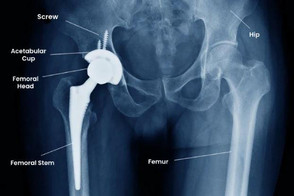

Total hip replacement involves removing the damaged femoral head and acetabular surface and replacing them with artificial components made of metal, ceramic, or polyethylene materials.